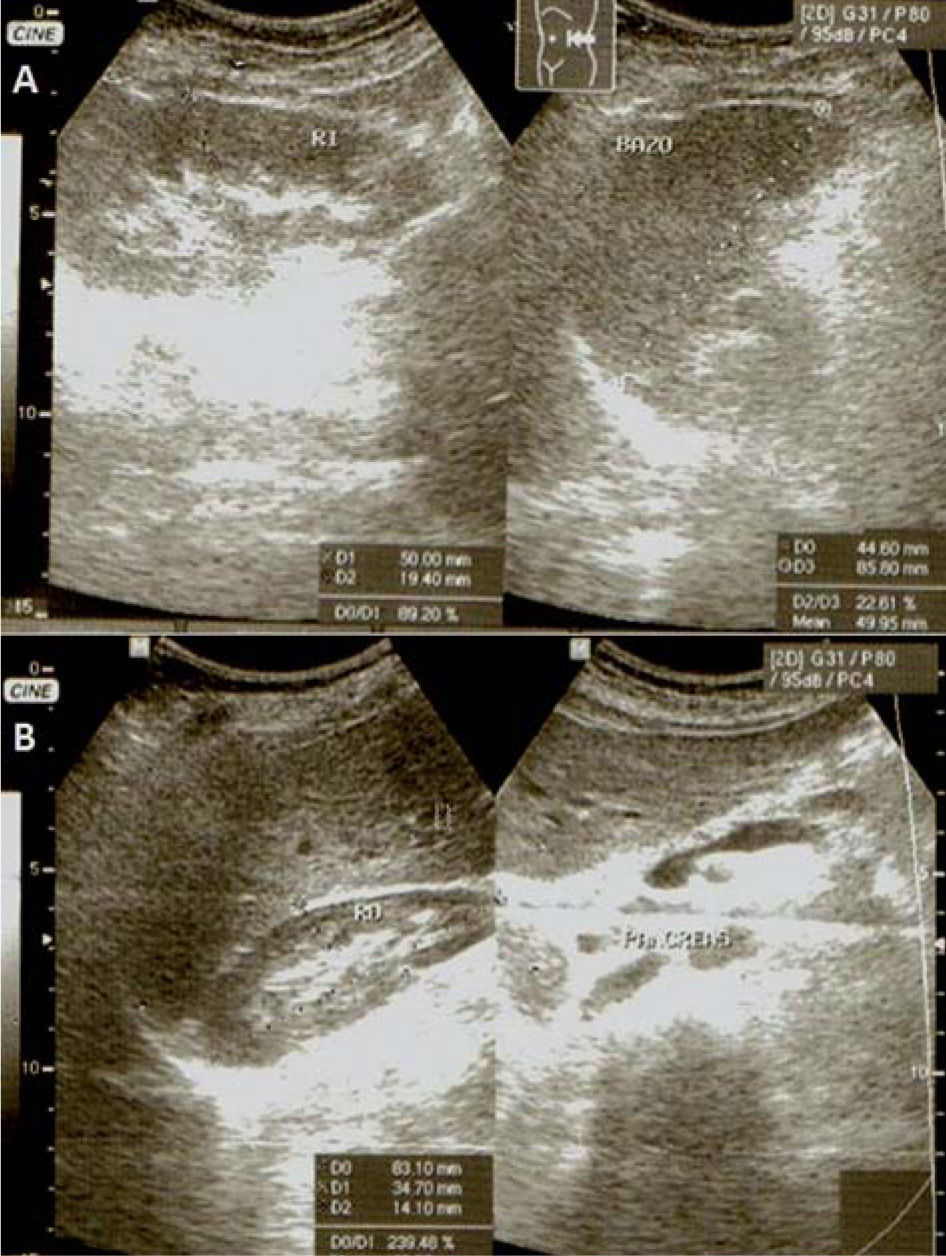

Caso ClínicoMujer de 69 años de edad, que consultó por masa abdominal, con historia de histerectomía con salpingo ooferectomia bilateral, 14 años antes, por múltiples leiomiomas uterinos, a quien se le encontró una gran masa, dolorosa a la palpación, a nivel de hipocondrio y flanco izquierdo, la cual fue documentada por ecografía abdominal y Tomografía Axial Computarizada (TAC), en retroperitoneo a la altura de la cola pancreática. La masa fue resecada, encontrándose numerosas adherencias que comprometían el riñón izquierdo y el colon.

Case historyA 69 year old woman presented with an abdominal mass. She had undergone hysterectomy and bilateral salpingooophorectomy for uterine leiomyomas 14 years previously. A large, tender mass was present in the left hypochondrium and left lumbar region, which was seen on abdominal ultrasonography and CT scan to be situated in the retroperitoneum near the tail of the pancreas. Surgery revealed that the left kidney and colon were involved. Pathology: The 950g, 12×11.5×10cm mass was composed of both solid and cystic areas. Histological and immunophenotypical findings indicated a diagnosis of extraovarian granulosa cell tumour.